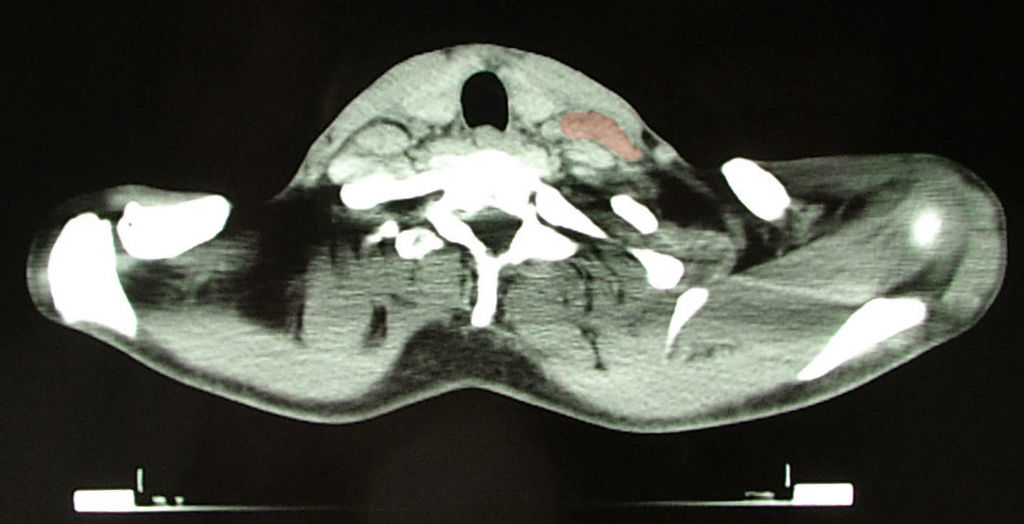

Patients with Hodgkin lymphoma (HL) typically present with enlarged cervical or mediastinal lymph nodes.